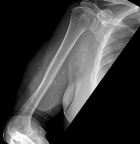

G.O. - 75 year old male with a right upper arm mass for 25 years; the mass never bothered him until a few months ago when he began having intermittent discomfort, he does not think the mass has grown recently